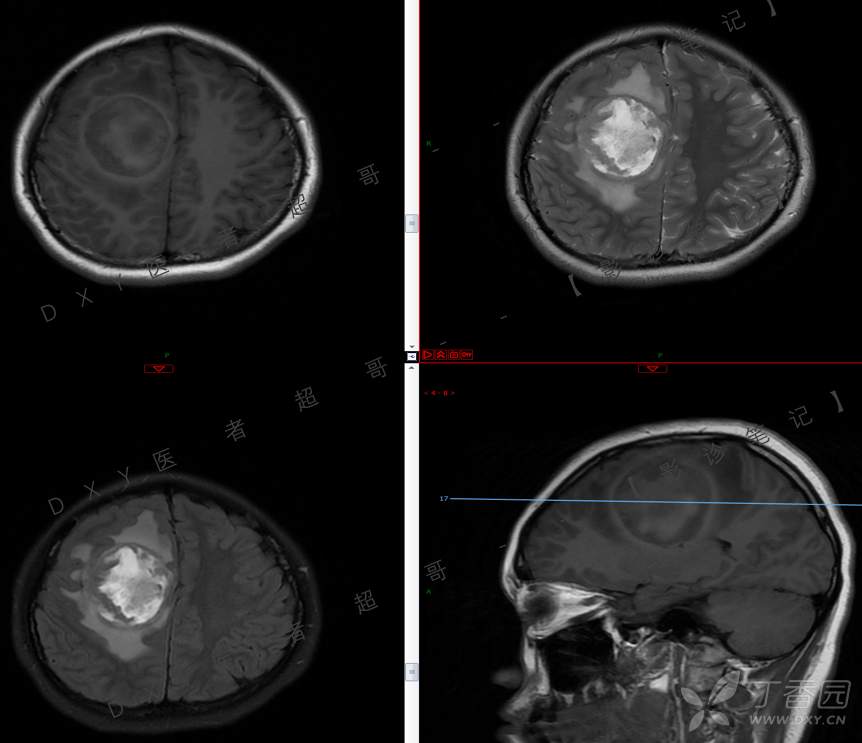

15岁少年,头痛10天,加重伴恶心、呕吐2天,究竟为何?回帖即可查阅病理。

主 诉:头痛10天,加重伴恶心、呕吐2天。

现病史:患者10天前无明显诱因出现头痛,间断发作,无恶心、呕吐,无肢体抽搐等,于当地医院就诊,体温37.4度,予以对症治疗,具体不详,后症状缓解,2天前患者上述症状较前加重,并感双眼胀痛及视物模糊,伴恶心、呕吐,呕吐数次,为胃内容物,再次于当地医院就诊,行颅脑CT考虑“右侧额顶叶病变”,现为求进一步治疗来我院急诊就诊,以“脑脓肿?”收入我科。患者病来精神差,饮食、睡眠欠佳,体重无明显变化。